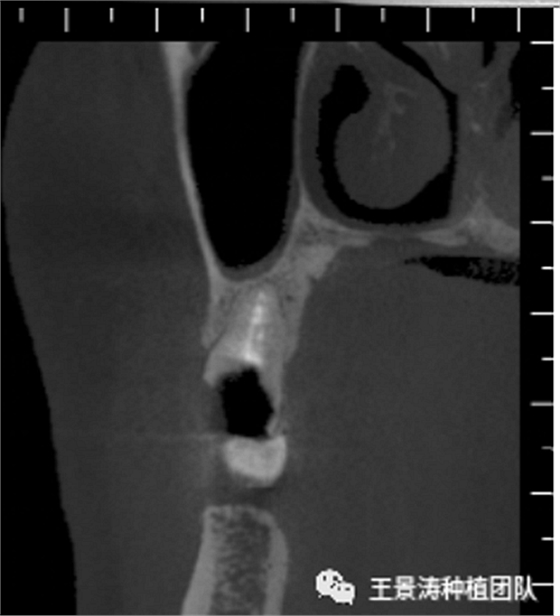

下述病例則是15區(qū)域的即刻種植,15因牙冠折斷于齦下,無法樁核冠修復,則考慮種植修復。但拍攝CBCT后發(fā)現(xiàn)根尖距上頜竇底距離較短?;颊邽槟贻p女性,無全身系統(tǒng)疾病且可利用上頜竇底與根尖皮質(zhì)骨雙側(cè)皮質(zhì)骨固位,且此位置可通過頰側(cè)軟組織減張技術(shù)獲得嚴密封閉牙槽窩。因其根尖距上頜竇距離較低,遂拔除15后行上頜竇內(nèi)提升,埋入式種植,最終修復的完成。